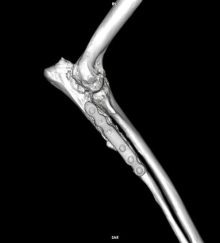

Treatment of a radius and ulna fracture in a Whippet

By Eastcott Referrals Orthopaedic Surgeon Fabio Frazzica A 1-year-old female Whippet presented with a distal diaphyseal, simple, transverse, closed ...